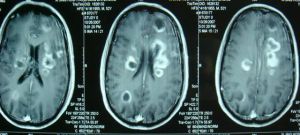

2、頭顱CT掃描可顯出擴大的腦室系統及腦實質性質,有助於鑑別是否有腦瘤等病。

(五)CT掃描:為對腦積水最直接的診斷方法,已替代了氣腦造影和腦室造影檢查。CT不僅可判斷腦積水的程度、推測阻塞部位、病因、是否合併畸形,對治療更有極大的指導意義。